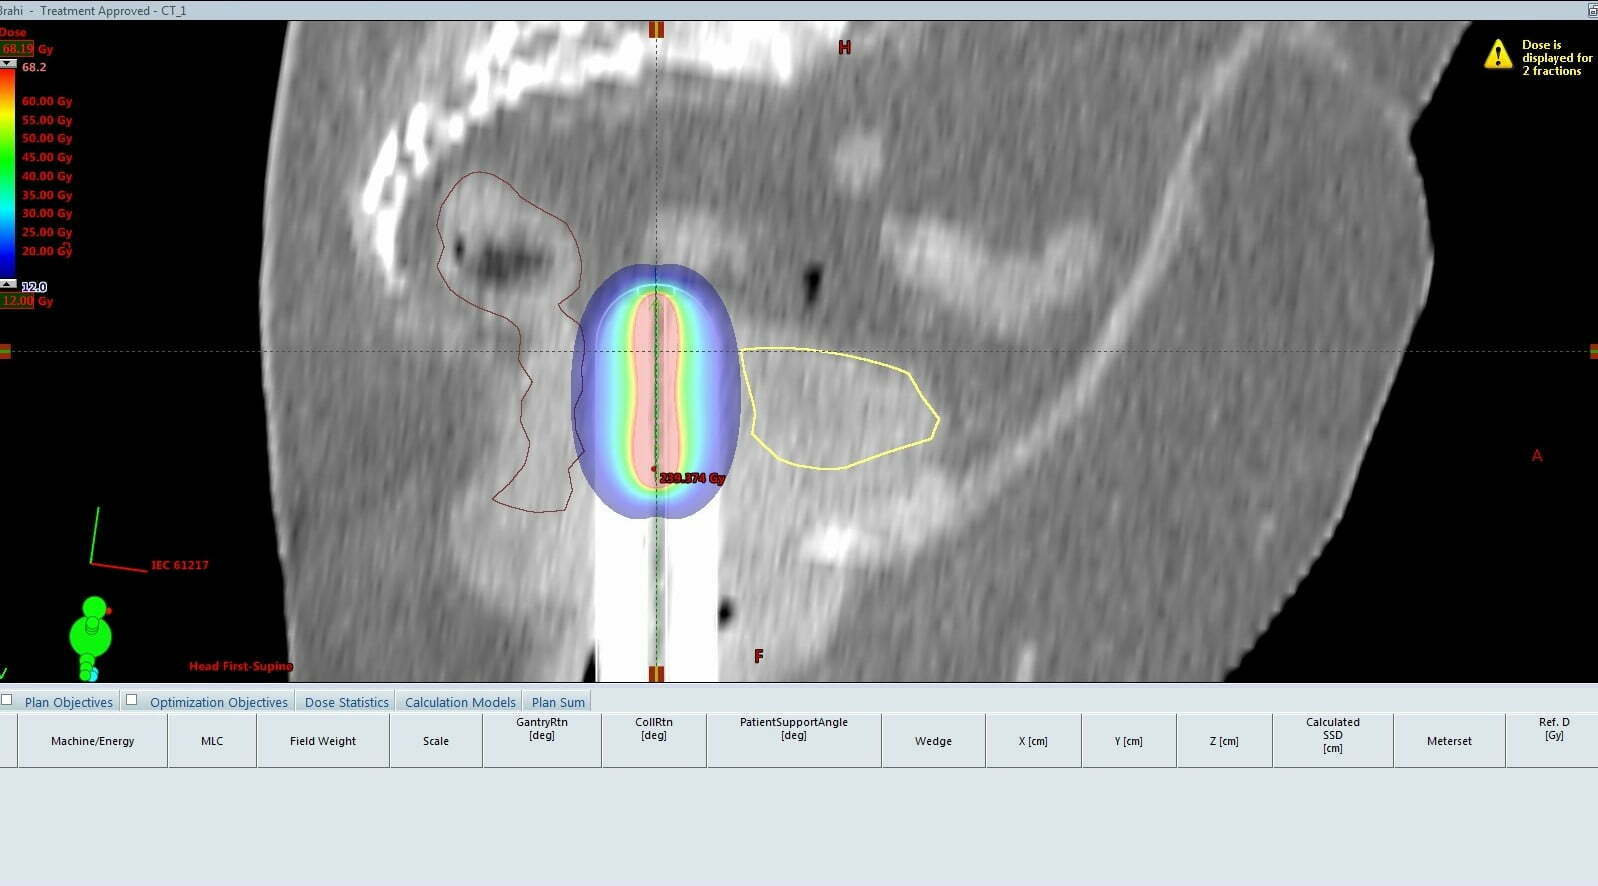

Procedura permite, pe de-o parte, iradierea puternică a tumorii prin introducerea unor surse radioactive în interiorul acesteia, dar, în același timp, datorită ghidajului imagistic 3D, protejează organele din jurul ei.

“Brahiterapia nu este o procedură foarte complicată, dar necesită multă atenție. Înaintea administrării dozei de radiații este nevoie de realizarea unui examinări cu ajutorul unui Computer Tomograf pentru a identifica foarte clar care este zona unde trebuie aplicat tratamentul, astfel încât să protejăm organele din jurul tumorii, în principal vezica și rectul. Vorbim de un tratament avansat, o intervenție invazivă, pentru care se folosește o tehnologie de ultimă generație care utilizează o sursă radioactivă puternică, Iridiu 192, dar care are un efect major asupra formațiunii tumorale. Sursa de iradiere produce raze gama care distrug celulele canceroase. Procedura propriu-zisă nu durează foarte mult, vorbim de o expunere de câteva minute, dar are rezultate foarte bune. De altfel, se realizează în cadrul unei spitalizări de zi”, epxlică Bogdan Ile – fizician la Asociația OncoHelp Timișoara.

“La Centrul OncoHelp am început să folosim această procedură în urmă cu o jumătate de an. Vorbim de un tratament avansat care se realizează în puține centre din tară. Numărul pacientelor care beneficiază gratuit de această procedură a crescut constant de atunci. Aparatul pe care-l folosim este de ultimă generație și permite acea tehnică de ghidaj imagistic, făcută cu ajutorul unui computer, asta pentru a ajunge în miezul țesutul tumoral, reducând astfel afectarea țesutului sănătos din jur și, implicit, reducând efectele secundare. Prin acestă procedură se poate chiar îndepărta un rest tumoral rămas în urma unei intervenții chirurgicale. Deocamdată, procedura se aplică în centrul nostru doar în cazul pacientelor cu cancer de col și corp uterin, dar în curând vom începe să o aplicăm și în cazul tumorilor cutanate”, spune dr. Anca Croitoru, medic primar radioterapie – Centrul Oncologic OncoHelp.